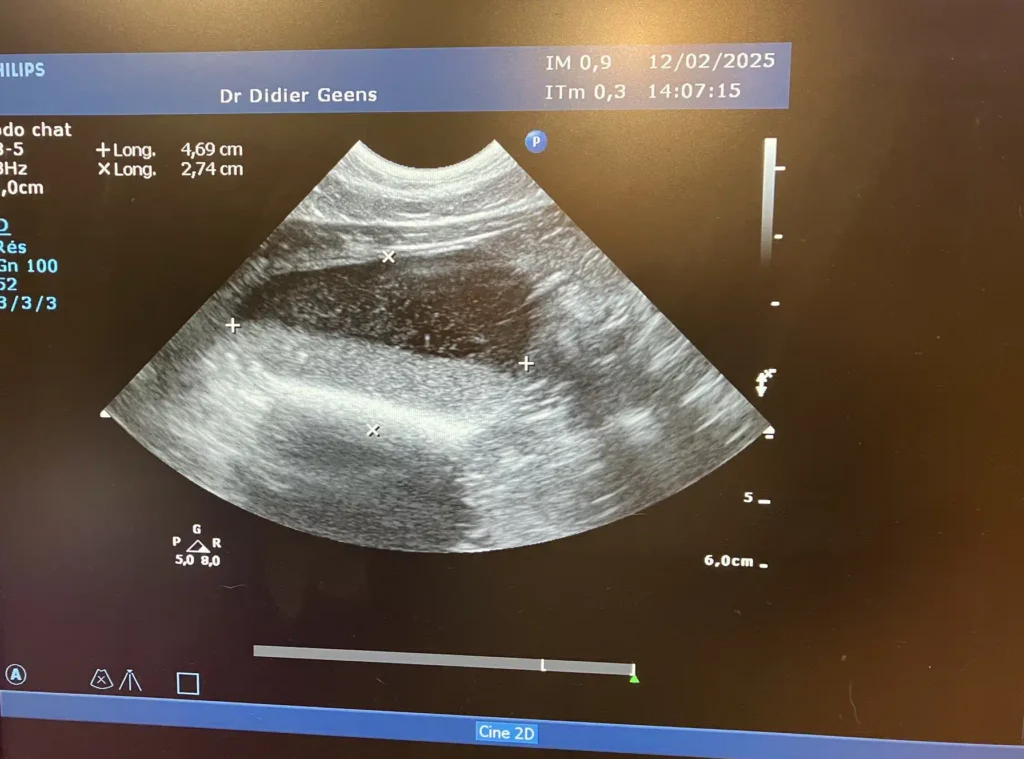

Mêmes symptômes que le chat sur la troisième photo, le chat va souvent dans son bac, fait des petites gouttes d'urine teintée de sang et parfois fait hors de son bac L'echographie montre la présence de deux calculs qui pourront soit être dissous par un régime adéquat ou devront être enlevés par chirurgie si ils ne disparaissent pas, alors que dans le premier cas un régime est très souvent suffisant.

Evolution:le régime instauré a été efficace, trois semaines plus tard les calculs avaient disparu